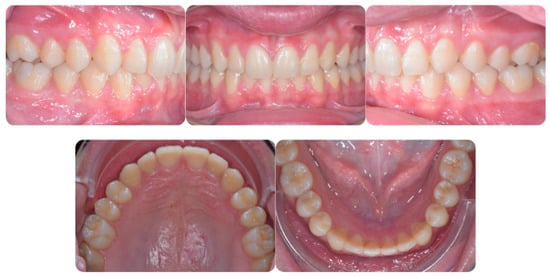

Figure 1 shows an initial stage of treatment—the upper arch with the absence deciduous canine no. 63. The malposition of the teeth, such as distorotation of the incisors, vestibuloposition of the right canine, as well as an irregular and incorrect shape of the upper arch, are noticeable.

Figure 1.

Pre-treatment records of the first patient.